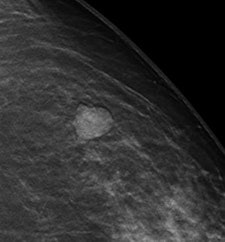

With tomosynthesis, low-dose images are obtained over a limited arc, and the projections are mathematically reconstructed into a series of sections with the hope that specificity and sensitivity will be improved. Initial work using tomosynthesis as an add-on to conventional 2D mammography suggested the potential for substantial improvements in specificity, the authors noted. They compared the diagnostic accuracy of 2D digital mammography with that of two-view (mediolateral and craniocaudal) and single-view (mediolateral oblique) tomosynthesis in an observer study involving two institutions: Cambridge and Capio St Göran's Hospital in Stockholm.

For diagnostic accuracy, 2D mammography performed significantly worse than two-view tomosynthesis (average area under receiver operating characteristic curve [AUC] = 0.772 for 2D, AUC = 0.851 for tomosynthesis; p = 0.021). The researchers found significant differences for masses and microcalcification (p = 0.037 and 0.049, respectively). The difference in AUC between the two modalities was significant only for the five readers with the least amount of experience (p = 0.03 versus p = 0.25 for readers with 10 or more years of experience). No significant difference was seen in reader performance when 2D mammography was compared with single-view tomosynthesis.